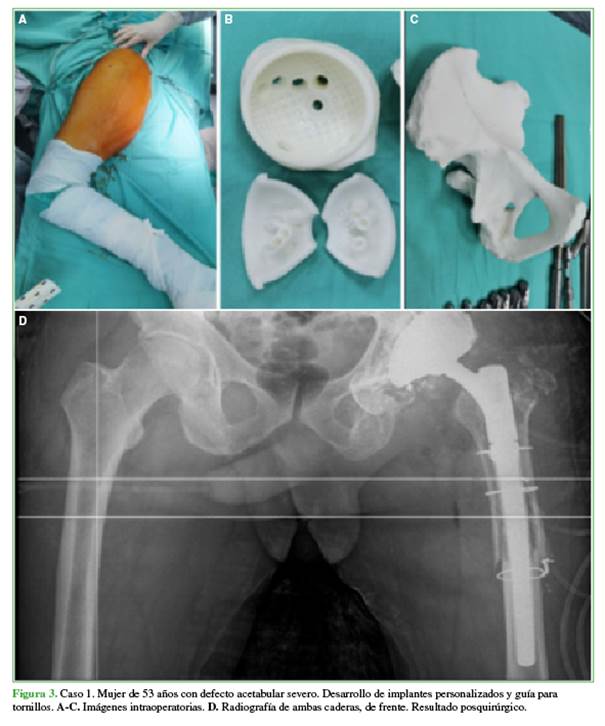

Nuestra serie incluyó 12 casos en los que se utilizó la impresión 3D para el diagnóstico, la planificación y el tratamiento. En ocho pacientes, el proceso se realizó íntegramente en nuestro hospital y, en los cuatro restantes, fue necesaria la intervención de otra institución para la impresión de implantes en titanio. Respecto a los instrumentos específicos para el paciente, se diseñaron guías de corte en cinco casos y un molde a medida para espaciador con cemento antibiótico. Se fabricaron tres implantes acetabulares a medida, dos de ellos requirieron la confección adicional de guías para la colocación de tornillos (Figura 3).

En cuanto a los pacientes, cinco eran mujeres y siete, hombres. La edad promedio era de 39 años. En los pacientes jóvenes (promedio 26 años), fueron más frecuentes la enfermedad tumoral o las secuelas, mientras que, en los mayores (promedio 60 años), lo más habitual fueron las complicaciones de artroplastia.

Se realizó la planificación digital en todos los pacientes utilizando los programas disponibles principalmente para mediciones y determinación de márgenes oncológicos, ángulos de osteotomía, cuantificación del volumen de injerto requerido o stock óseo disponible para la colocación de implantes. Los procedimientos quirúrgicos se desarrollaron según lo planificado y con los biomodelos impresos. No fue necesario ningún procedimiento intraquirúrgico adicional a los planificados. En los pacientes con enfermedad tumoral y aloinjerto, el plan quirúrgico inicial se modificó luego de la disponibilidad de los biomodelos; estas modificaciones consistieron principalmente en la localización de los planos de resección (Figura 4). En casos de reconstrucción con aloinjerto, fue posible la conformación de dos equipos quirúrgicos simultáneos, uno a cargo de la resección oncológica y otro, del procesamiento del injerto de banco; ocurrió algo similar en el caso del espaciador de cemento a medida, donde un equipo estuvo a cargo de la limpieza, mientras otro conformaba el espaciador.